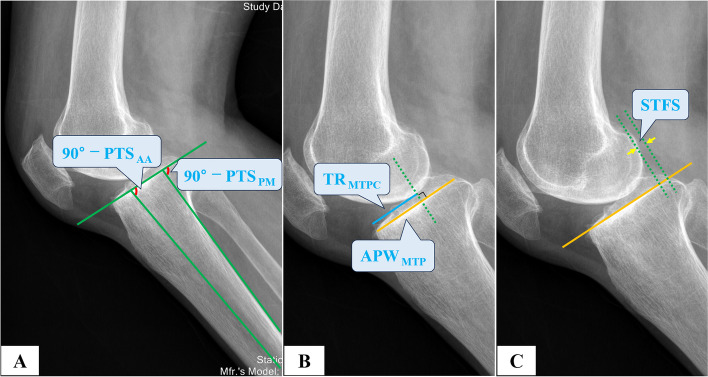

Methods: We analyzed 306 knees retrospectively using preoperative hip-to-ankle anteroposterior standing (APS) radiographs, anteroposterior (AP) and lateral knee radiographs, AP valgus stress (VS) force radiographs, and standard orthogonal MRI. Based on the intraoperative visualization, the knees were grouped into ACL functionally-intact and ACL functionally-deficient (ACLD) groups. The diagnostic validity and reliability were calculated based on the radiograph parameters such as hip-knee-ankle angle (HKA), medial proximal tibial angle (MPTA), lateral distal femoral angle (LDFA), posterior tibial slope (PTS), sagittal tibiofemoral subluxation (STFS), coronal tibiofemoral subluxation (CTFS), joint line convergence angle (JLCA), the maximum wear point of the proximal tibia plateau (MWPPT%), and MRI parameters including ACL grades and MWPPT%.